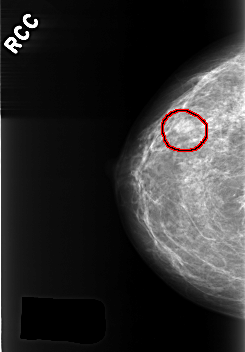

C_0363_1.RIGHT_CC

RIGHT_CC LINES 4216 PIXELS_PER_LINE 2936 BITS_PER_PIXEL 12 RESOLUTION 50 OVERLAY

FILE: C_0363_1.RIGHT_CC.OVERLAY

TOTAL_ABNORMALITIES 1

ABNORMALITY 1

LESION_TYPE MASS SHAPE OVAL MARGINS CIRCUMSCRIBED

ASSESSMENT 3

SUBTLETY 4

PATHOLOGY BENIGN

TOTAL_OUTLINES 1

BOUNDARY